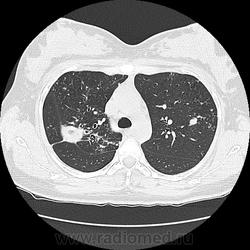

Ага, сначала вот эта с каверной пришла 12.05, а потом с туберкуломами 19.05 с интервалом в неделю, закон парных случаев, обе только родили, род.дом в панике, я в шоке

Протекает почти бессимптомно при больших деструктивных изменениях в легочной ткани. Поэтому в клинических наблюдениях целесообразно кратко указывать: жалобы, начало и тяжесть заболевания, гемограмму. Об этом недавно шла дискуссия на http://www.radiomed.ru/cases/pomogite-differentsirovat-pozhaluista

В том то и дело, что анамнез скудный, жалоб нет или врала, жила себе поживала девушка, забеременела, родила, а в правом легком "дырка".